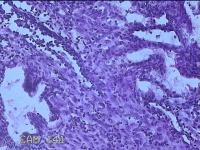

子宫腔内膜组织

性别

女

年龄

44岁

临床诊断

子宫异常出血、甲亢、轻度贫血

一般病史

阴道流血20天,加重1天。

标本名称

大体所见

灰白暗红色不规则碎组织3x2.8x0.3cm一堆。